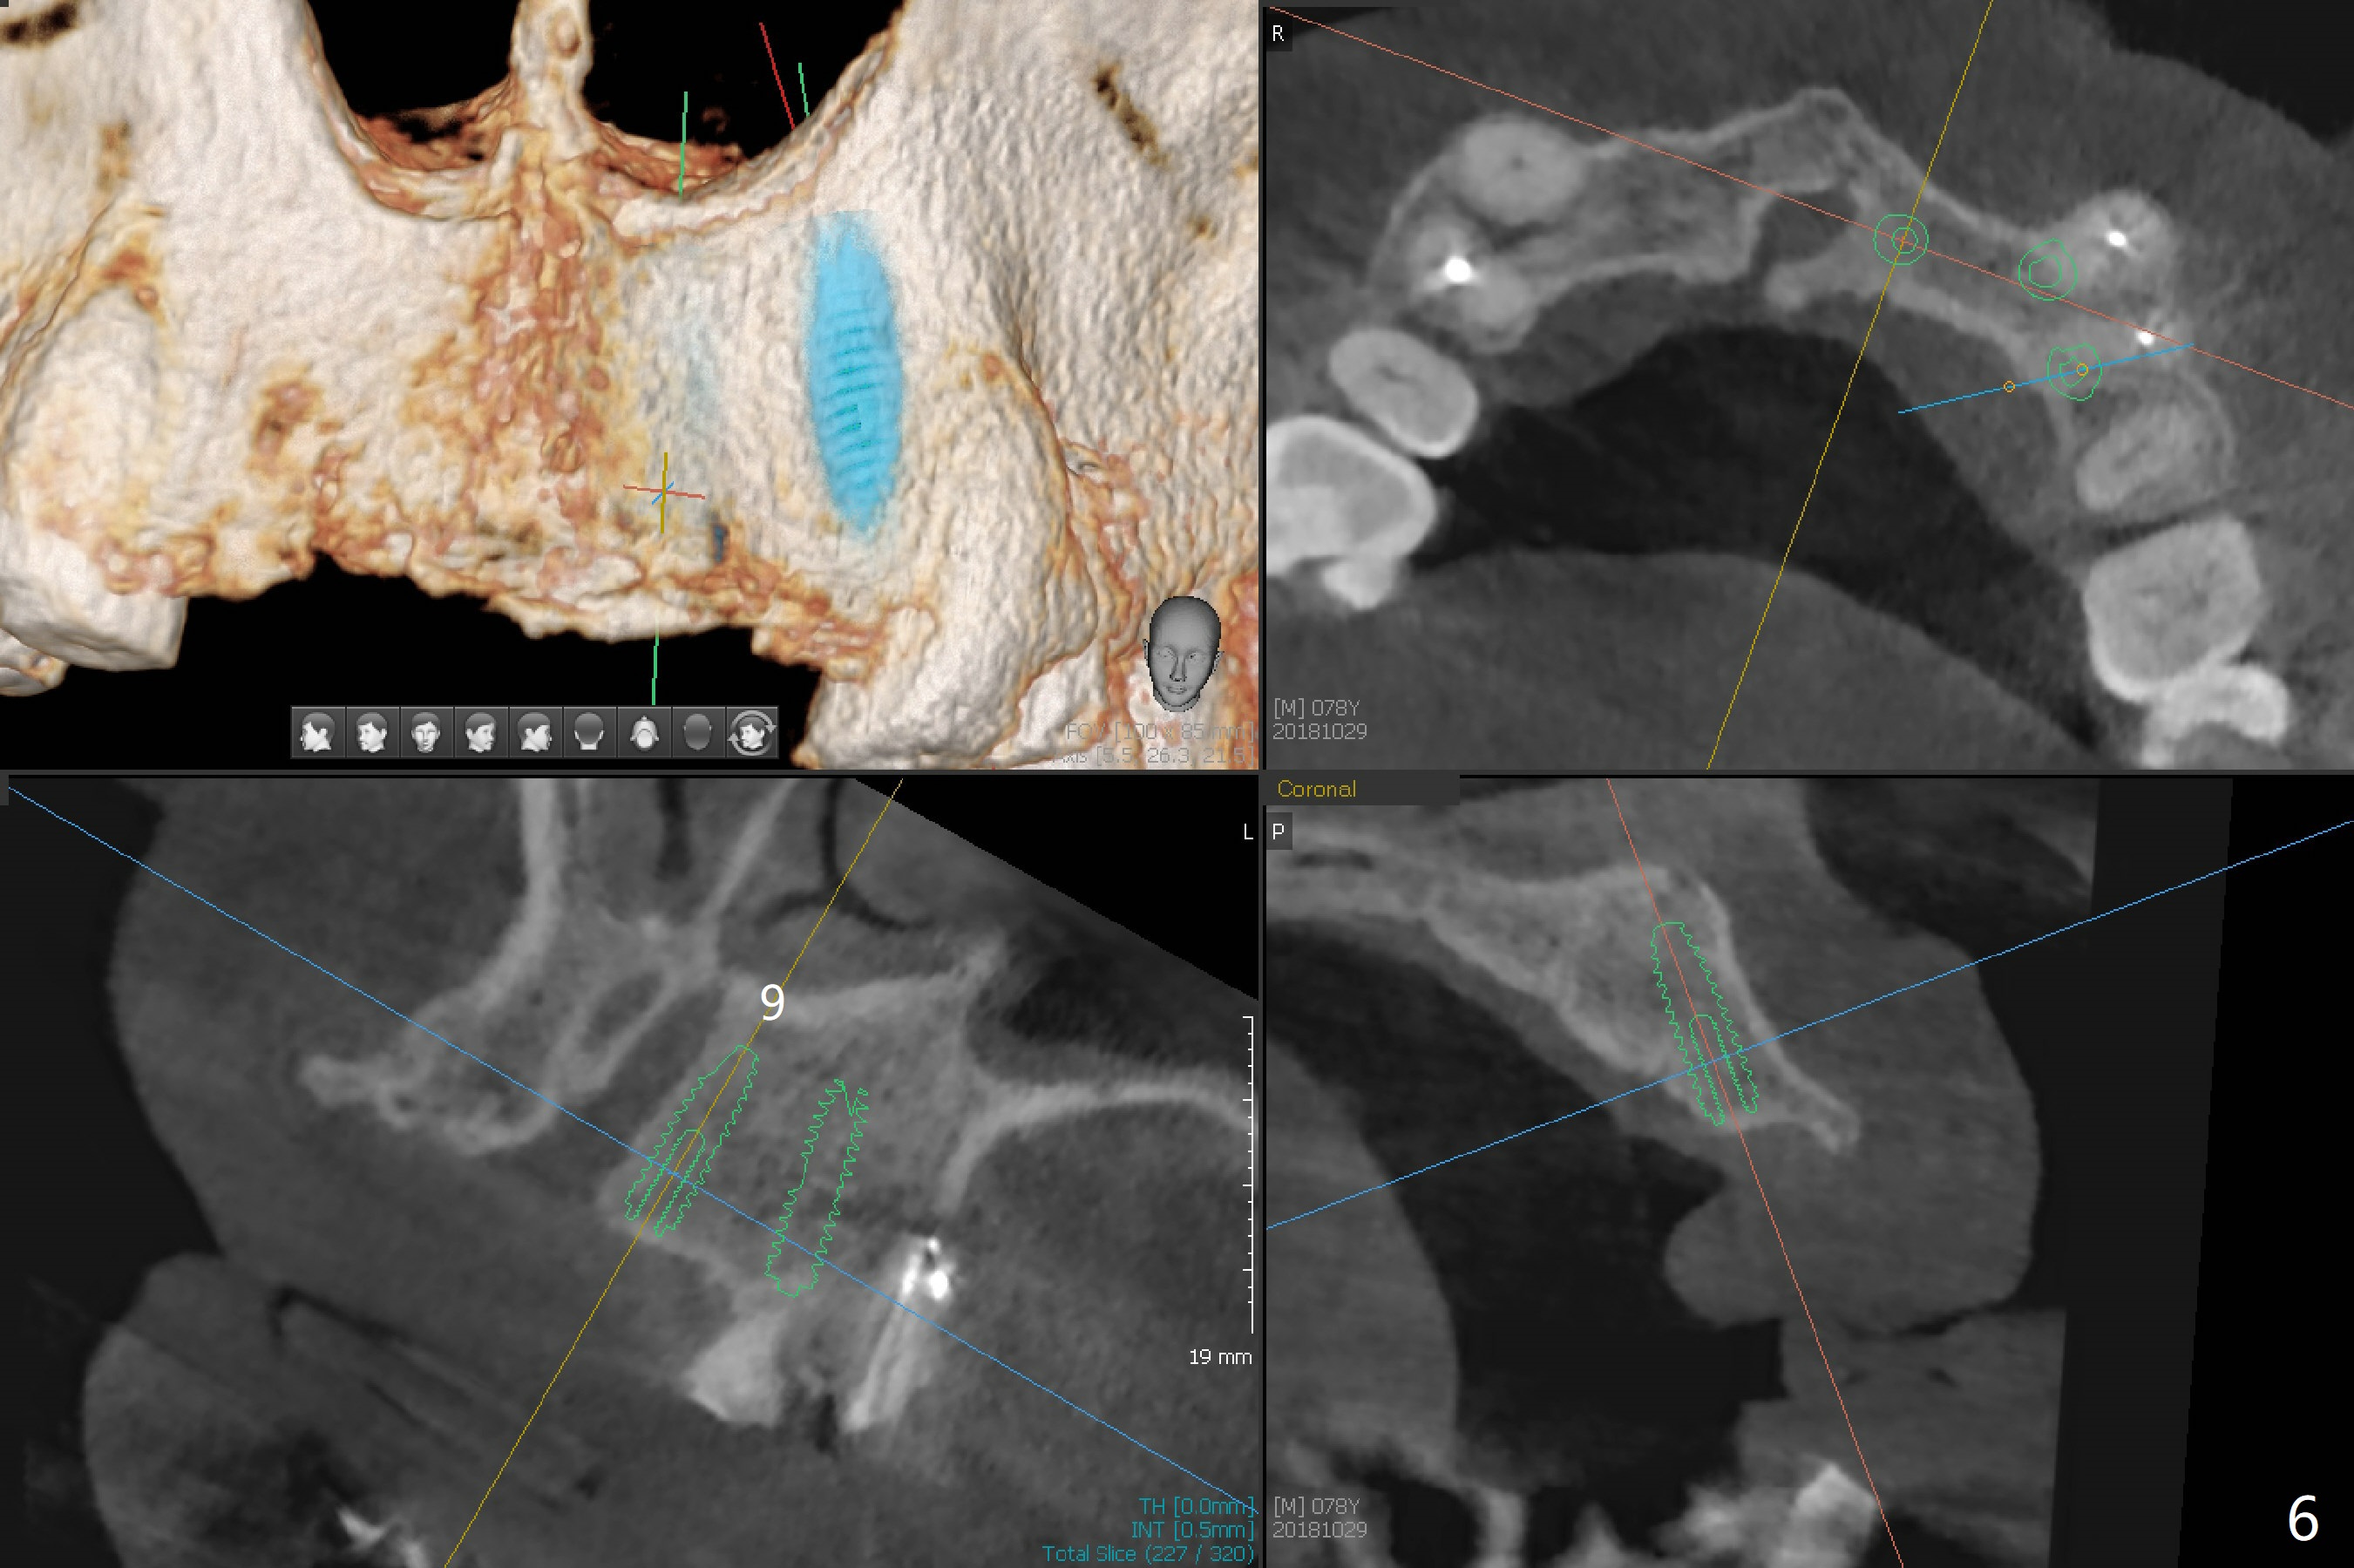

A 78-year-old man's 8 unit FPD dislodges (#5-12, Fig.1). Three of 4 abutments seem to be non-salvageable (#6,11,12 fractured equigingival, extraction, immediate implants). For restoration, implant will be placed at #8 and 9 as well. Implant FPDs will be fabricated at #6-8 and 9-11 (Fig.2) with #5 (with build up or prefabricated post) and 12 single unit crowns to better withstand deep overbite and overjet. After discussion with lab, a major change will be implants to be placed at #7 and 10 instead of #8 and 9 (narrow ridge). The implant at #7 will be a 1-piece (3 mm in diameter), whereas the rest 2-piece (3.5 mm). The abutment of IS 1-piece implant is 10 mm in length, while that of DIO's 5 mm. The former will be used if the vertical space is sufficient.